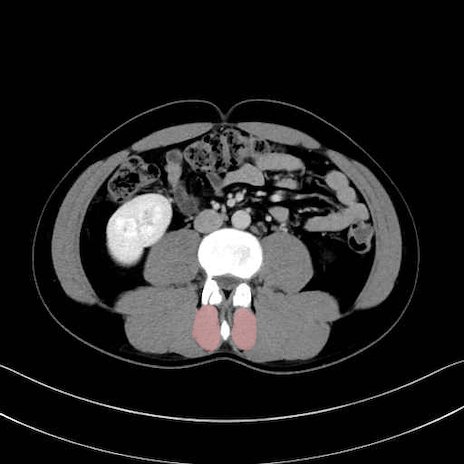

多裂筋 (Multifidus)